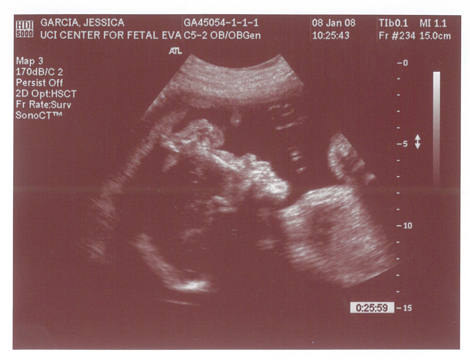

Yes we got a new dsmer coming into the world soon. We got our ultrasound today and its gonna be a boy. And shes a lot further along then we had originally thought. Shes due on April 15th which puts her at almost 6.5 months, (and really not showing it.) He weighs currently ~2lbs. He even opened his mouth while on camera which was really cool.

Here are the pics.

Pic 1: The babies head profile

Pic 2: Mouth is open!